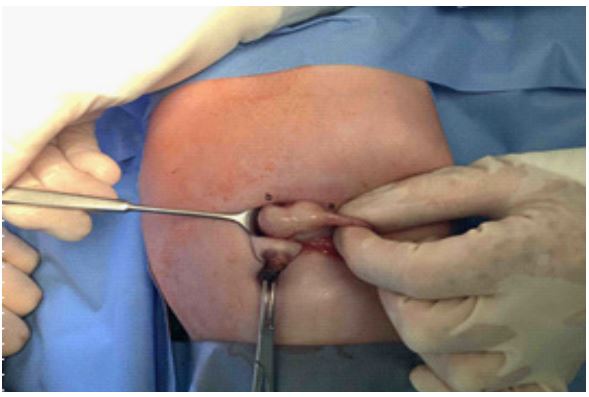

The delivery was performed at 37 completed weeks of gestation via Cesarean section due to velamentous insertion. The neonate was postnatally vital, with APGAR scores of 7/8/9 and birth weight of 3295 grams (64th percentile). Immediately after birth the infant exhibited respiratory distress and an increased oxygen requirement, necessitating the initiation of CPAP- therapy. Placement of a gastric tube was not feasible, and an X-ray revealed an esophageal blind pouch (Figure 1).

An open surgical approach was chosen to create a precise surgical access and reach the affected area of the esophagus. A type 3b esophageal atresia was found.

The esophageal atresia was carefully opened, and the ends of the healthy esophagus were identified. Utilizing a microsurgical approach, the two ends of the esophagus were connected (Figure 2). To provide additional support and stability during the anastomosis, a transanastomotic tube was employed to splint the esophagus. Following successful esophageal anastomosis, a thorough inspection for potential leaks was performed. No signs of leakage were detected.

Figure 2: lIntraoperative image of esophageal atresia. The proximal and distal ends of the esophagus are located close together. The tracheoesophageal fistula is yellow looped. The azygos vein (blue looped) is kept free.